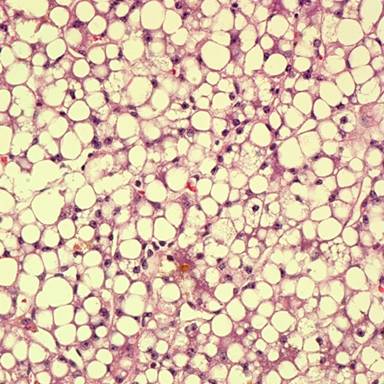

Analysis of serum amino acids revealed elevated levels of glutamine, alanine and proline. In addition, lysine, ornithine and arginine were mildly elevated. Citrulline, cystine and rest of the amino acids including carnitine levels were normal. Results of microbiologic testing, including PCR-based testing for herpes simplex, varicella zoster and Epstein-Barr virus in the cerebrospinal fluid, and India ink preparation for Cryptococcus and other fungi were negative. The liver biopsy showed prominent diffuse macrovesicular steatosis with moderate signs of cholestasis (Figures 2 and 3).

Figure 2. Liver biopsy showing diffuse macrovesicular steatosis. |

Hyperammonemia is well established cause of encephalopathy and coma. In our patient, hyperammonemia progressed to coma with no previous history of liver disease. Hyperammonemia can be primarily seen with hereditary defects in urea cycle enzyme function or can be seen secondary to acute or chronic liver disease, organic acidemias, carnitine deficiency, Reye’s syndrome, infections with urea-splitting organisms, such as Proteus mirabilis and iatrogenic causes including transjugular intrahepatic portosystemic shunting, total parenteral nutrition, and adverse drug effects from valproate, carbamazepine or asparaginase [9, 10, 11, 12, 13, 14, 15, 16]. It has also been described following bone marrow transplantation, lung transplantation or after chemotherapy for leukemia [5, 6, 7, 8]. In the present case, there was no evidence of underlying liver disease or acute hepatitis. Although fluid cultures were positive for Escherichia coli, blood cultures were negative and patient continued to worsen in spite of treatment of infection. The patient was not on any drugs that have been implicated in hyperammonemia. Although the patient had elevations of certain serum amino acids, elevations were inconsistent with any specific urea cycle defect and gene sequencing following recovery of the patient did not reveal any urea cycle defect. The presence of normal urine organic levels eliminated the possibility of methylmalonic, propionic, or isovaleric acidemia as well as primary carnitine deficiency and other defects in fatty acid oxidation as etiologic factors for this hyperammonemia. However, the patient had severe malnutrition and had co-existing intra-abdominal infection at the time of her presentation with hyperammonemia. Also the liver biopsy showed prominent diffuse macrovesicular steatosis with moderate signs of cholestasis (Figures 2 and 3). Our patient most probably fits the profile of “idiopathic hyperammonemia” which is defined based on a plasma ammonia level greater than twice the upper limit of normal, with relatively normal other liver function tests, and in the absence of inborn errors of metabolism or other identifiable causes. Although Reye’s syndrome can mimic idiopathic hyperammonemia, it is rare in adults and our patient had no prodromal viral symptoms or history of aspirin ingestion to support the diagnosis. Also the absence of significant elevation of lysine makes Reye’s syndrome less likely [3].